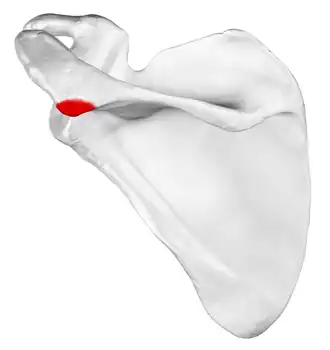

![]() Left scapula, posterior view. Acromion shown in red. | |